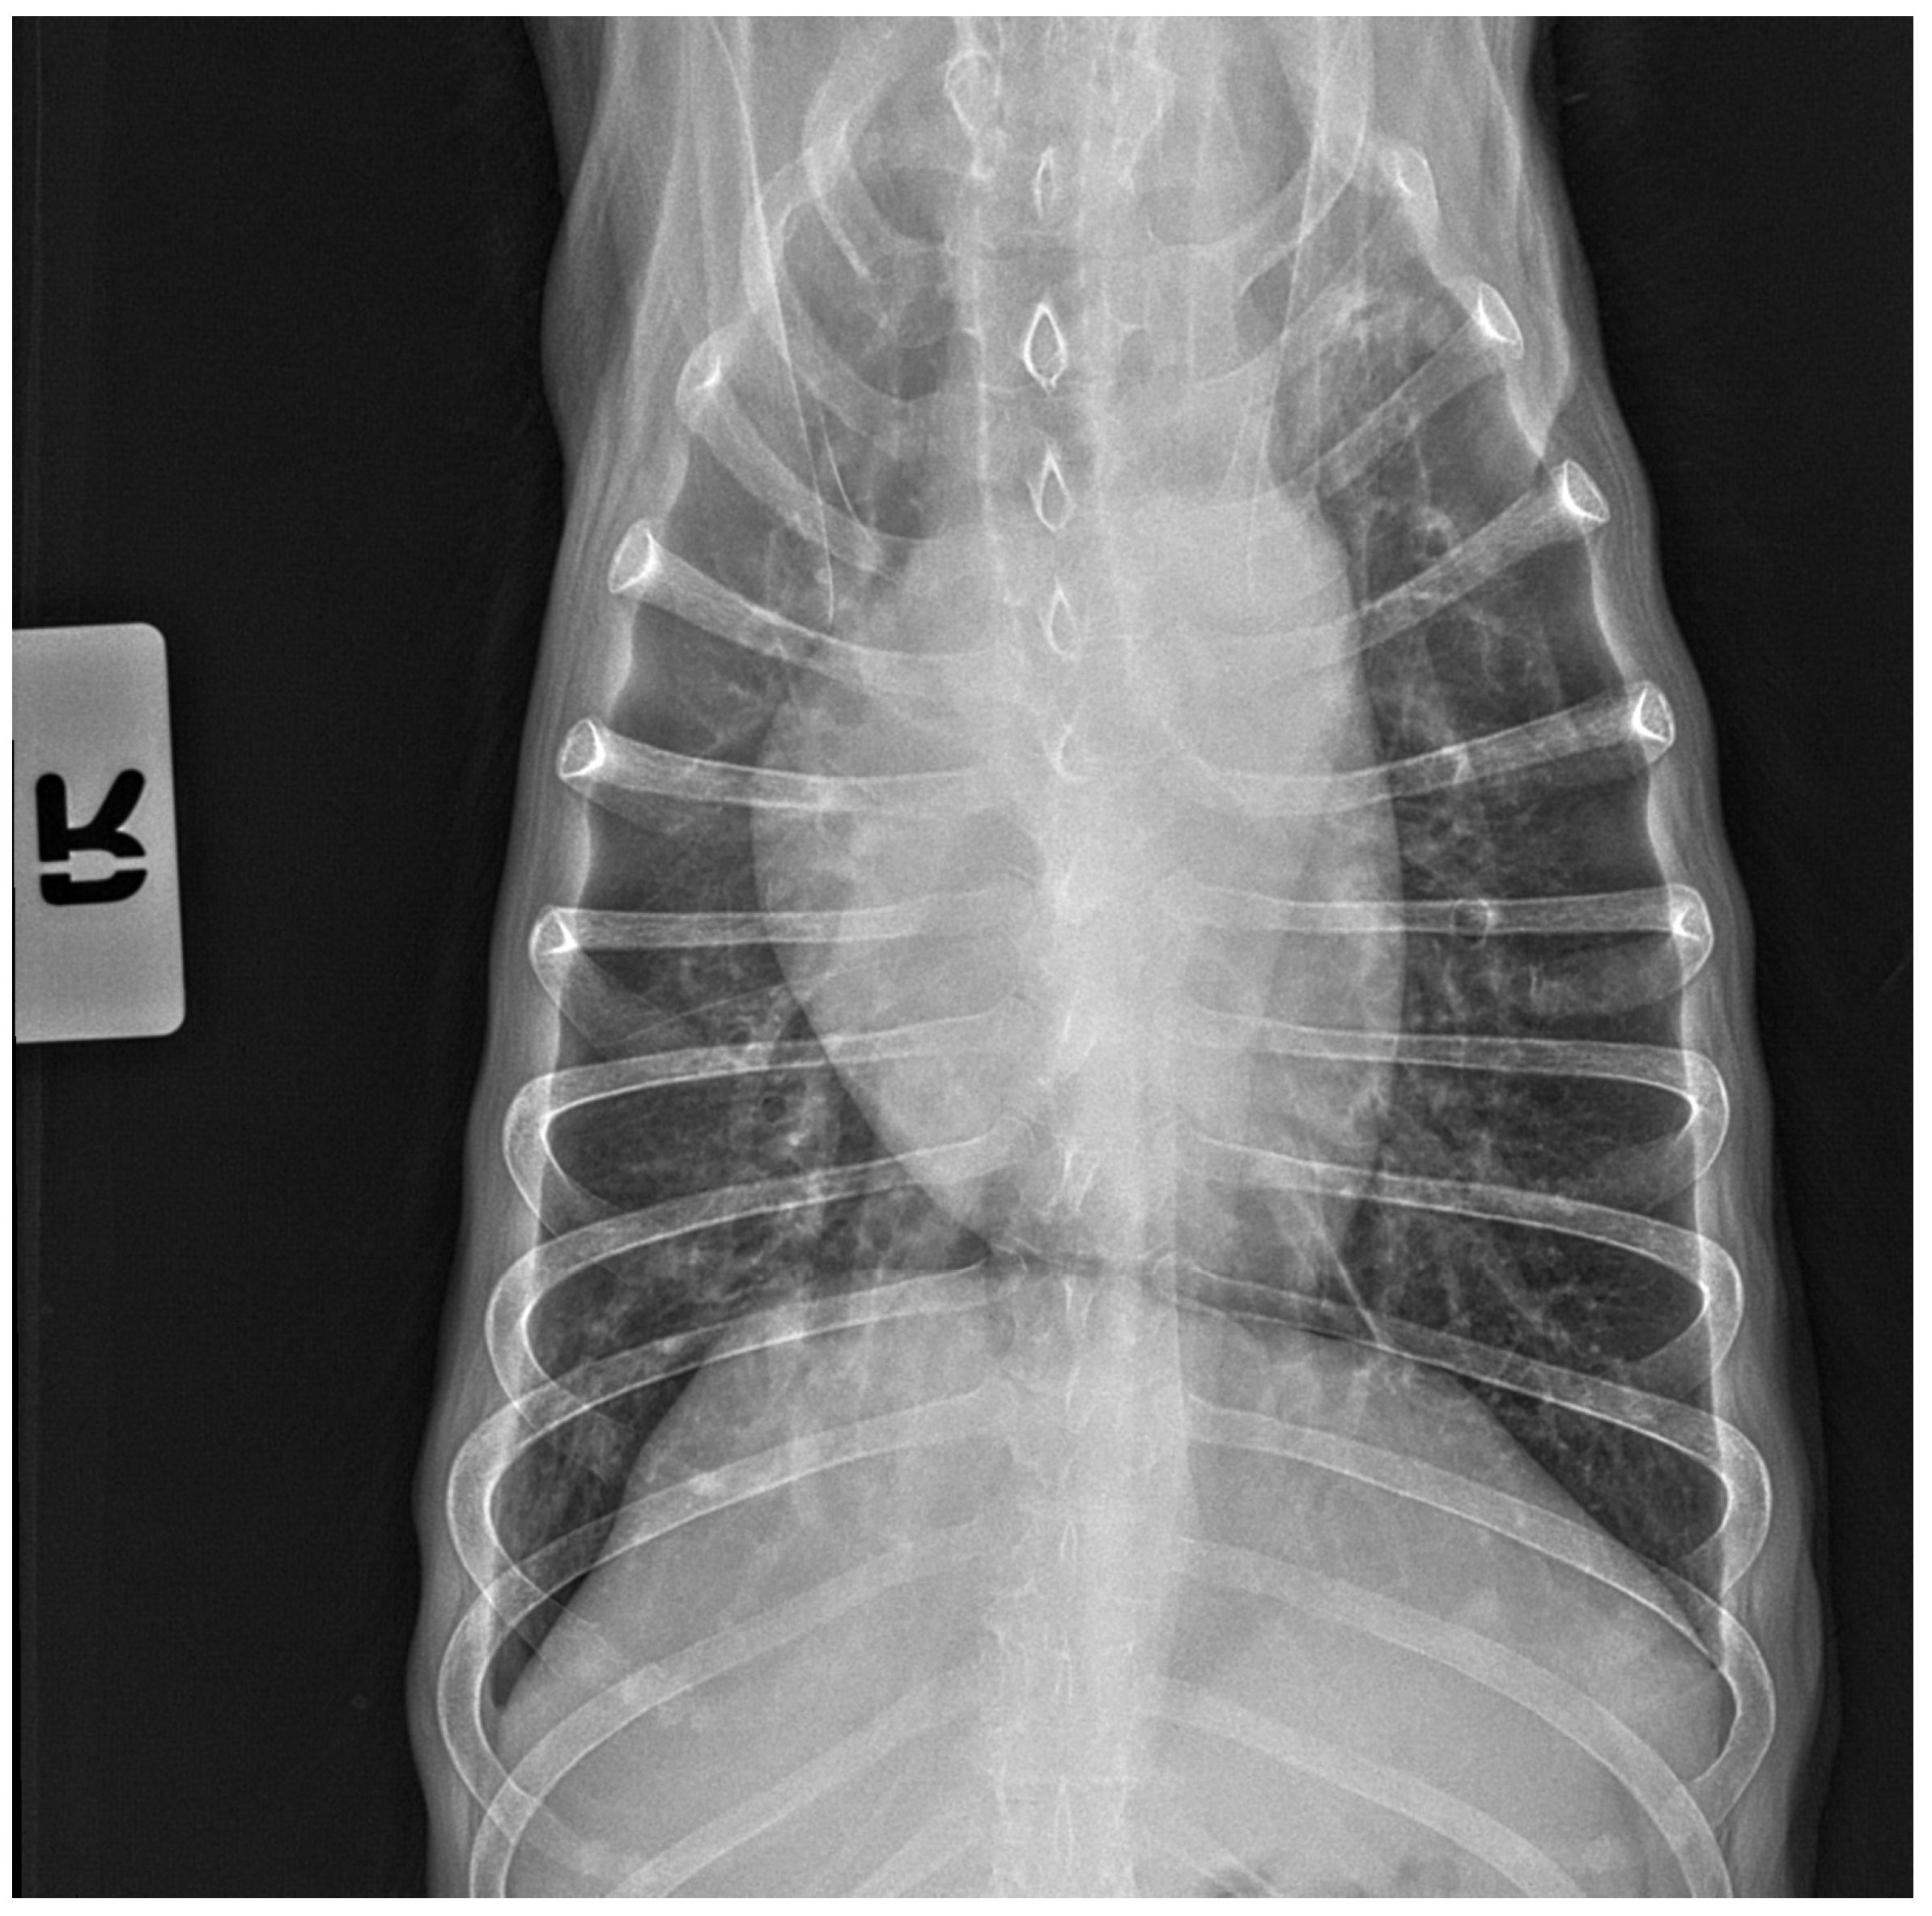

No pathological changes were detected in the lung parenchyma image in the X-ray (Figure 1 and Figure 2). The ultrasound examination revealed in all views a normal, aerated lung pattern. The pleural line was intact, and A-line artifacts were present (Figure 3). The sliding sign was also observed. Echocardiography revealed a mild thickening of the mitral valve leaflets and a slight regurgitation (Figure 4) of this valve. The size of the heart chambers was within the normal range, and myocardial contractility was normal.

Figure 2.

The thoracic X-ray image in the anteroposterior (AP) position shows no pathological alterations within the lung parenchyma and cardiac silhouette.